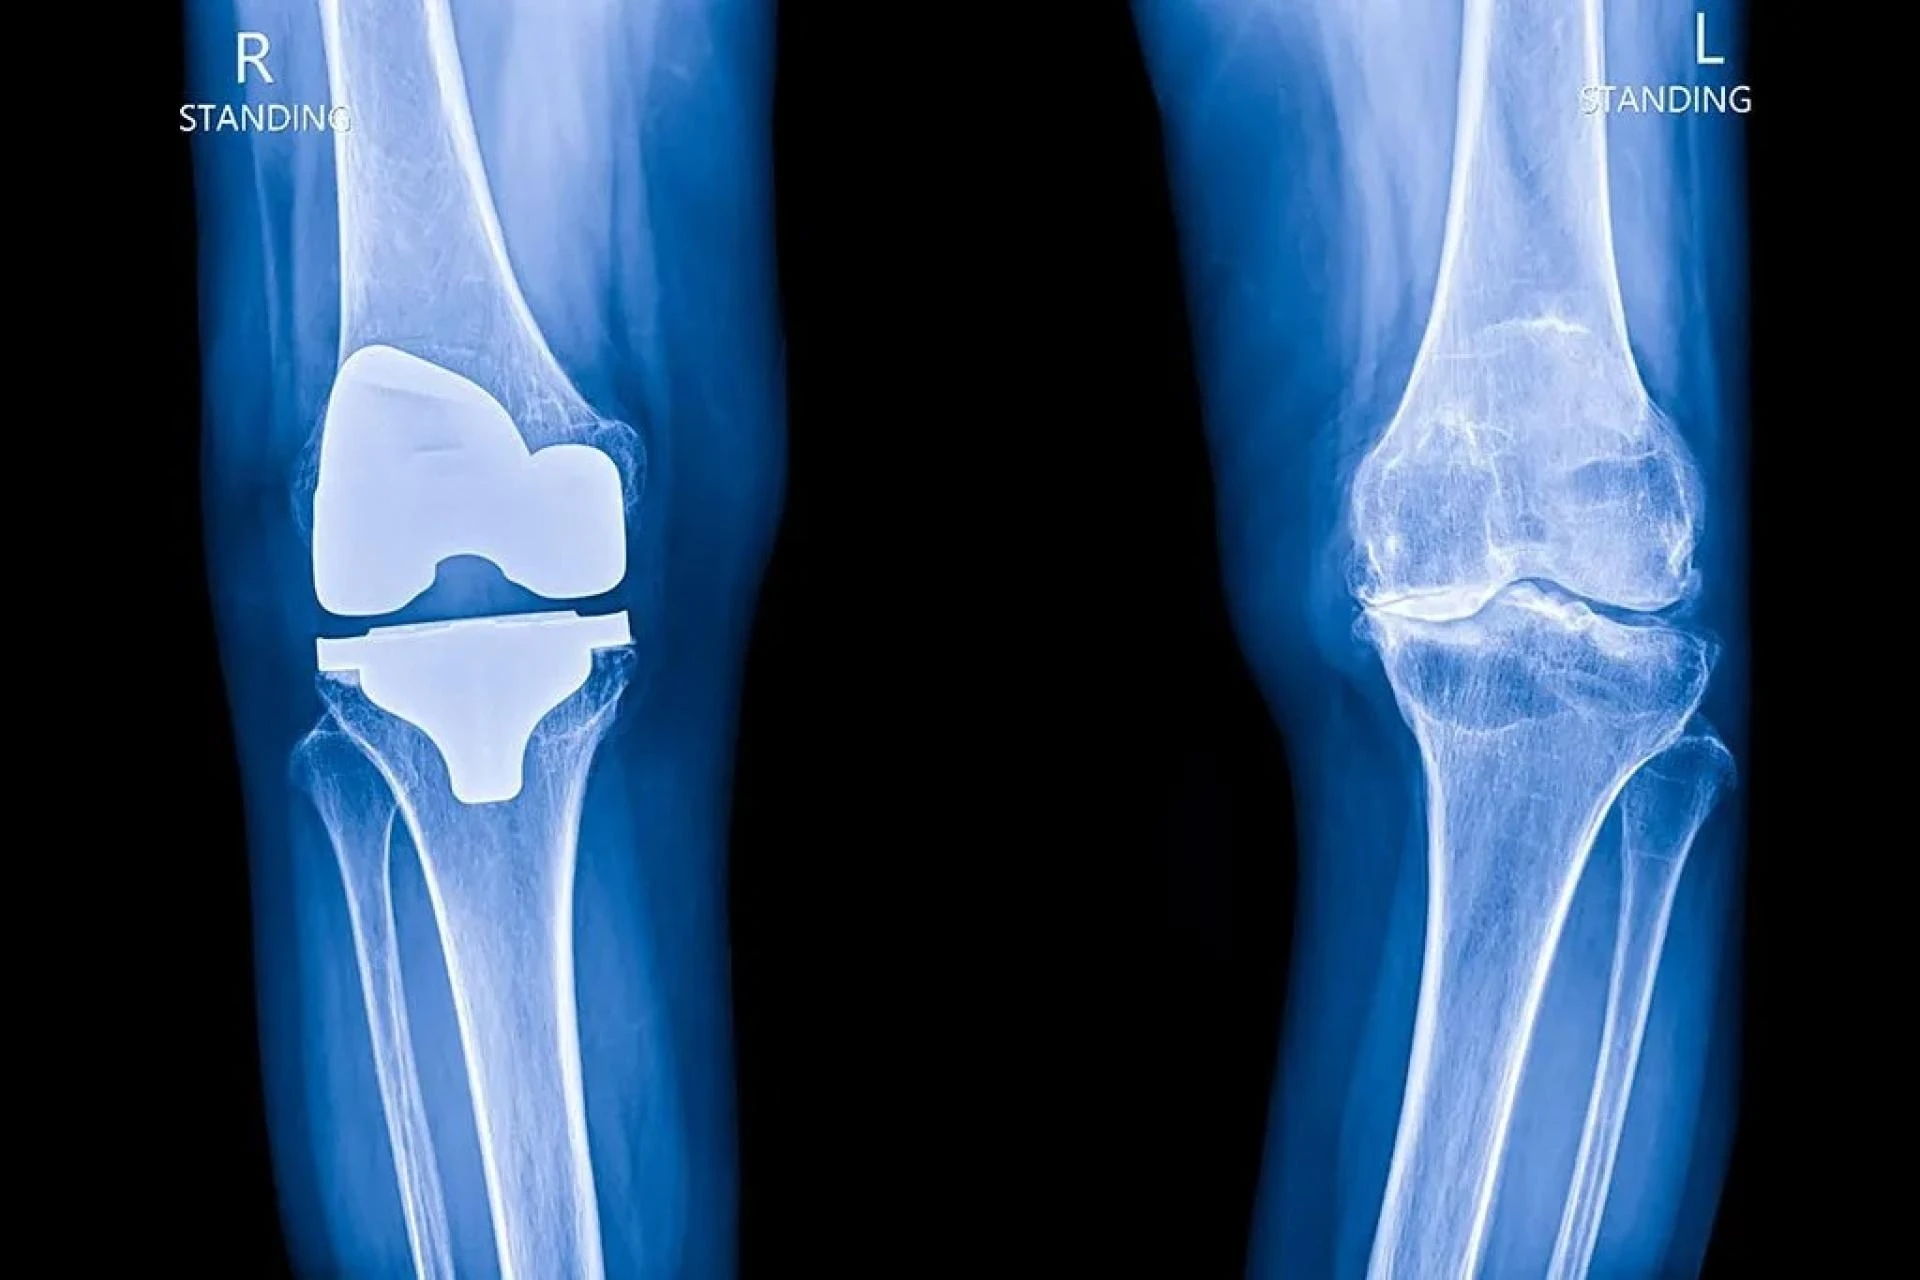

Robotic knee replacement is an advanced surgical procedure that helps doctors replace a damaged knee joint with high accuracy. Unlike traditional knee replacement, this procedure uses a robotic system to guide the surgeon, ensuring precise placement and alignment of the new knee joint. This improved accuracy can lead to better movement, less pain, and a quicker recovery.

The robotic system does not perform the surgery on its own. Instead, it assists the surgeon by creating a detailed 3D model of the knee, helping to plan the procedure based on the patient's specific needs. During surgery, the robotic arm helps in making precise cuts and placing the implant in the best position.

Robotic knee surgery in mumbai is a highly advanced procedure that improves the accuracy and effectiveness of knee replacement. Unlike traditional methods, this surgery uses robotic-assisted technology to help surgeons perform the procedure with extreme precision. The robotic system creates a detailed 3D model of the knee, allowing for better planning and personalized treatment based on the patient’s specific bone structure. This ensures that the knee implant is positioned perfectly, leading to smoother movement, reduced pain, and a faster recovery.